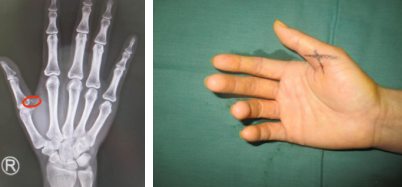

何大妈赶紧让家人开车带她来到sararz,当天接诊的是手外科四病区的张继朝医生,令张医生惊讶地是,何大妈受伤都快两个月了,竟然还没手术取出手中残留的异物,幸好何大妈的右拇指并未发炎。经过拍片检查后发现碎玻璃的位置紧贴拇指的血管及神经。何大妈着急地问道:“医生,能取出来吗?”张医生回答:“您放心,我们一定帮您取出来,不让它再继续待在里面了!”。何大妈感慨几经波折,总算找对了地方。

3月10日,何大妈的手术终于安排上了。张医生医疗组在她的右手拇指上做了一个小切口,经过细心剥离血管和神经,探查到了那片小小的碎玻璃并成功取出。不到一个小时,手术便顺利结束了。返回病房后,何大妈的心情特别好。别看碎玻璃小,却像块石头一样压在人的心里,不畅快呀!